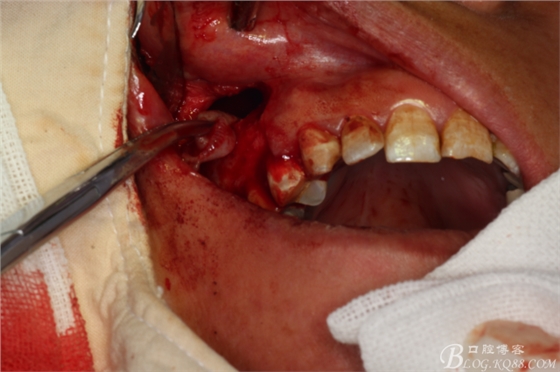

圖11.囊壁摘除后,暴露的16腭側(cè)根尖有少許牙膠尖超填

圖12.高速牙鉆截取16腭根3mm.